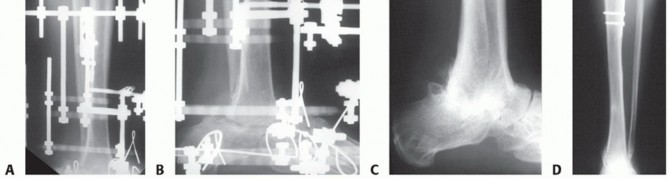

FIG 1 • The extent of bone loss and infection will determine the reconstruction. A. Extensive infection of the talar dome compromising tibial talar arthrodesis. B. Complete necrosis of the talar body. C. Necrosis of the entire talus. D. Necrosis of the plafond and talus. E. Traumatic ejection or crushing of the talar body. F. Traumatic ejection or crushing of the talus.*

Acute talar bone loss and subsequent AVN and infection will present a cascade of hindfoot reconstruction problems (FIG 1).

Open fracture-dislocations of the talus are high-energy injuries that cause disruption of the blood supply by dislocation, ejection of fragments, and fracture through the neck of the talus. This causes AVN of the body or entire talus, which is susceptible to infection (see FIG 1).